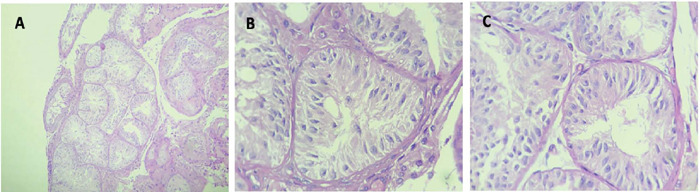

The 46, XY differences in sex development (DSD) caused by 5-alpha reductase type 2 (5ARD2) often presents with bilateral undescended testicles, otherwise normal internal reproductive structures, prostate hypoplasia and undervirilized male genitalia. Notably, as one of the few DSDs where fertility is possible, the clinical presentation of this disease is diverse, and reported cases of assisted reproduction are scarce. The fertility potential, reproductive counseling and treatment depend on the clinical presentation of this DSD, especially the testicular position and urethral anatomy. The influence of the timing and modality of surgery for hypospadias and cryptorchidism should be considered. We aimed to describe the use of microscopic testicular sperm extraction (micro-TESE) in this population. We provide a descriptive analysis of how micro-TESE is a possible potential tool for assisted reproduction in 5ARD2-deficient patients. A 33-year-old male who underwent bilateral orchidopexy, phalloplasty, and urethroplasty at the age of 9 years presented successful sperm retrieval but failed embryo development after intracytoplasmic sperm injection. Testicular histology revealed late spermatogenic arrest. A 28-year-old male with bilateral orchidopexy, phalloplasty, and urethroplasty at age 25 with unsuccessful sperm retrieval. Testicular histology revealed a Sertoli cell-only pattern. 5ARD2-deficient patients are singular patients. The potential impact of the time between atypical genitalia procedures and orchidopexy on fertility should be highly considered. Micro-TESE is a technique that may be used to assist azoospermic patients in this population. Early orchidopexy and penile and urethral corrections should be considered key strategies to preserve the fertility potential of 5ARD2 patients.